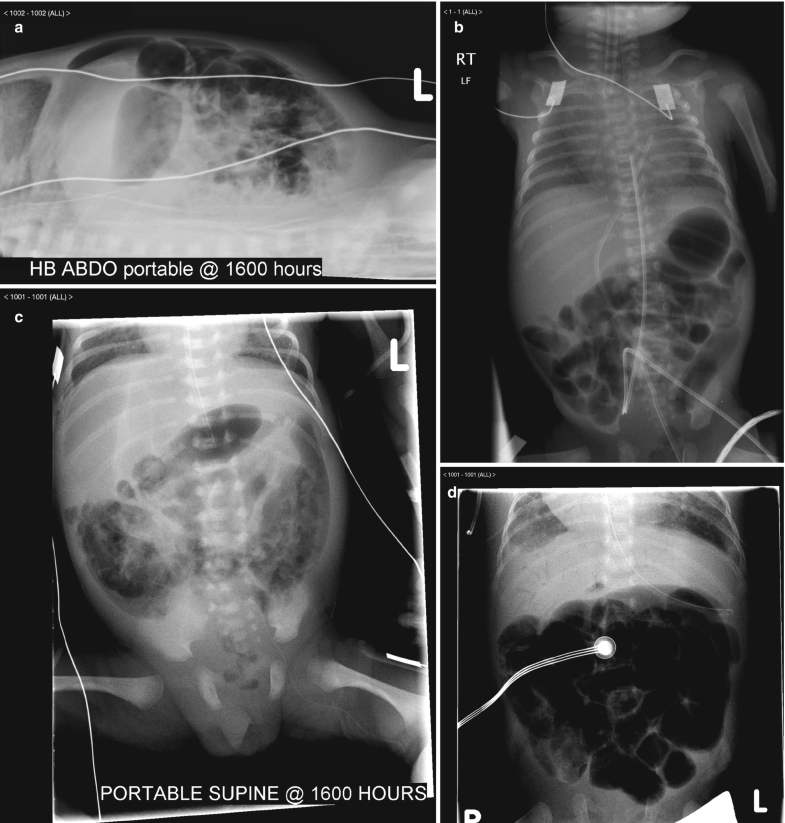

Request a Demo 14 Day Free Trial Buy Now. A non-obstructive bowel gas pattern is now pretty much a defunct Radiologic term which means the findings are not sufficiently specific for bowel obstruction. A physiological stool burden means you have a normal amount of stool in your colonNothing bad. A lack of precision in this report may adversely affect patient care. Your doctor may order this to see what the cause of your abdominal pain or symptoms is. 1 9 10 Nonobstructive bowel dilatation is a rare entity and may be the result of intrauterine fetal compromise congenital chloride diarrhea Hirschsprung disease congenital.

ICD-10-CM Code for Other intestinal obstruction K5669 ICD-10 code K5669 for Other intestinal obstruction is a medical classification as listed by WHO under the range - Diseases of the digestive system. Im only addressing the first question. I suggest you look the article by Dean Maglinte MD titled something like The Non-specific Bowel Gas Pattern. It could be an obstruction or. A non-obstructive bowel gas pattern is now pretty much a defunct Radiologic term which means the findings are not sufficiently specific for bowel obstruction.

I suggest you look the article by Dean Maglinte MD titled something like The Non-specific Bowel Gas Pattern. What is a non obstructive bowel gas pattern. Male w Scoliosis There is a mild broad-based dextroscoliosis of the thoracolumbar spine There is a gastrostomy tube in place and a partially obstructive bowel gas pattern. The radiology report is the primary means of communication between the radiologist and the referring physician. Non-Specific Bowel Gas Pattern.

A non-obstructive bowel gas pattern is now pretty much a defunct Radiologic term which means the findings are not sufficiently specific for bowel obstruction. You will see this in the conclusion or the impression of the report of an abdominal X-ray. Legal intervnt w unsp gas law enforc offl injured subs. Male w Scoliosis There is a mild broad-based dextroscoliosis of the thoracolumbar spine There is a gastrostomy tube in place and a partially obstructive bowel gas pattern. The patients with complete hemivaginal obstruction have significantly different presentation when compared to those with.

Idiopathic sleep related non-obstructive alveolar hypoventilation. Request a Demo 14 Day Free Trial Buy Now. R143 is a billablespecific ICD-10-CM code that can be used to indicate a diagnosis for reimbursement purposes. This will fall in between the normal bowel and grossly abnormal blocked bowel. Now getting to the non specific bowel gas pattern.

This is the American ICD-10-CM version of R143 - other international versions of ICD-10 R143 may differ. Cases demonstrating single or multiple loops of borderline or slightly dilated small intes- tine 25 cm to 3 cm with 3 or more air-fluid levels on upright or decubitus films. Functional diarrhea K591. Mild small bowel stasis abnormal but nonspecific pattern is defined as those. Non obstructive bowel pattern on abdominal X-ray means no evidence of bowel obstruction normal.